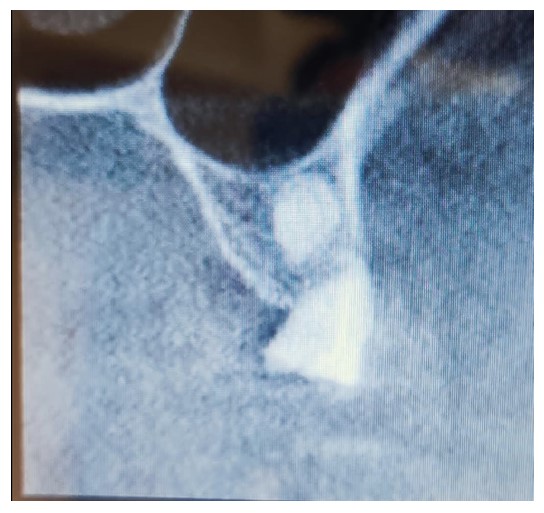

A 62-year-old female patient presented for maxillary rehabilitation with an implant-supported fixed prosthesis. Clinical examination revealed a failing conventional fixed partial denture extending from tooth #14 to #21, exhibiting significant gingival recession and radiographic evidence of periapical pathology. Preoperative cone-beam computed tomography (CBCT) using a Planmeca ProMax 3D unit demonstrated a well-defined radiopaque lesion measuring 1.5 × 1.3 cm adjacent to tooth #16, with a buccal-palatal width of 8.2 mm and bone density measuring 1250 Hounsfield units (Fig. 1).

Preoperative OPG showing a radiopaque lesion on the right posterior maxilla.

Preoperative scan showing the location of the lesion noted when reviewing scans after implant failure.